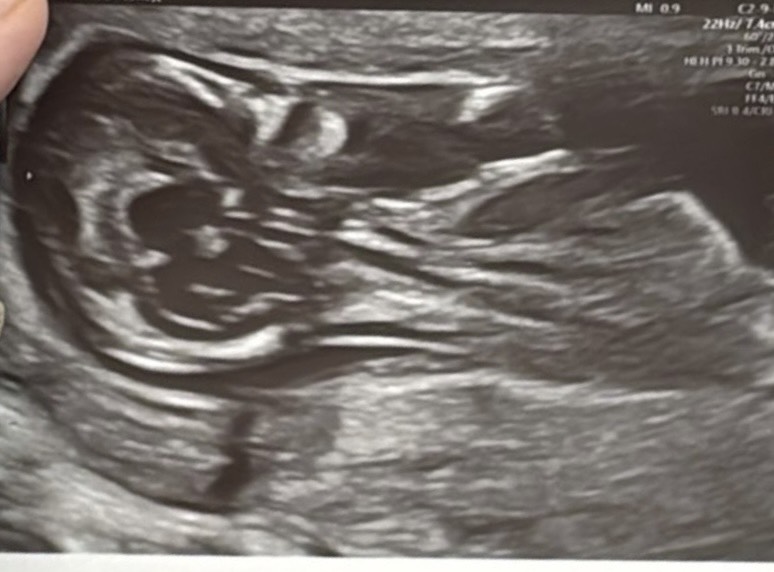

вспомнила как после этой фотографии заплакала что доча родиться не красивой😭👋🏻(я видела только красивые фотки с узи поэтому не была готова к тому что мне могут дать неудачную)

Мы все так ждали второй скрининг чтобы её увидеть в итоге нам вручили это до сих пор смотрим и пытаемся разобрать что где😂😂😂

Когда на 18 неделе беременности после 3 д УЗИ дали снимок, я показала маме и свекрови с такой гордостью, а свекровь сказала: Ой что да страшненькая обезьянка! Это на нашу принцессу красавицу🥲 я так переживала